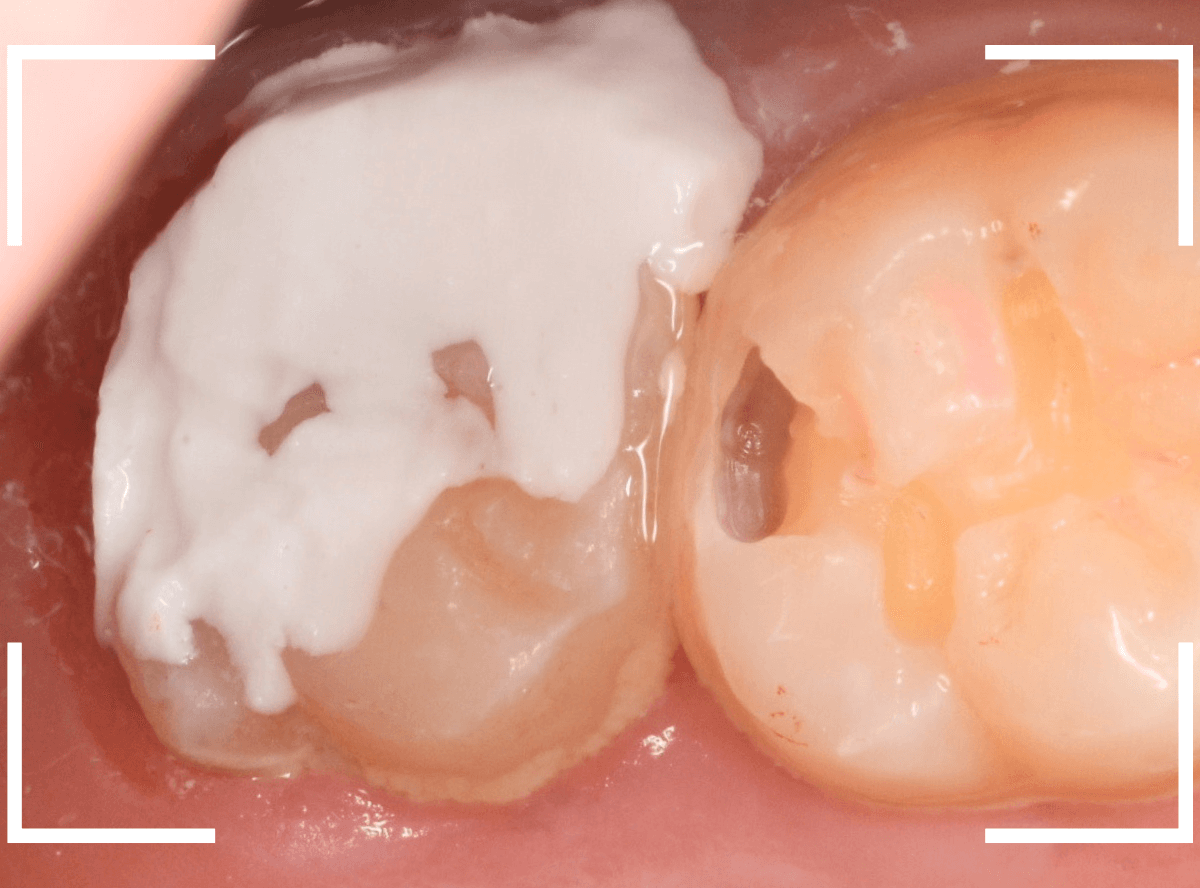

Case.7 治療を中断して、神経に達するほど虫歯が進行した

こちらは正確には「気づかない」ではなく、症状がないため治療途中の虫歯を放置してしまった方の例です。

つめていたセメントが剥がれ、大きな穴が空いています。

レントゲン写真で確認します。

青い部分が神経、赤い部分が虫歯です。

虫歯を放置してしまったため、歯の神経まで虫歯が達しています。

また、手前の歯の歯肉の中まで、虫歯は大きく進行しています。

慎重に虫歯を除去します。

手前の歯は神経の処置をしているため、どれだけ虫歯が進行しても症状はなく、歯肉を除去しながら深い虫歯の処置をしています。

ここまで虫歯を除去しても、染色液で染めだすと赤く染まってきます。

神経に触ってしまわないがとても怖いですが、取り残してしまうと治療の意味がなくなってしまいますので、より慎重に虫歯を除去します。

奥歯の虫歯をなんとか全て除去できましたが、神経が一部顔を覗かせている状況です。

こうなると、治療後に痛みが出て、神経を除去しなければいけない可能性があります。

神経を保護するお薬をつめて、セメントで蓋をします。

あとは、手前の虫歯の治療をしながら、痛みが出ない事を祈るばかりです。

絶対に治療を中断しないよう、念を押したのは言うまでもありません。。。